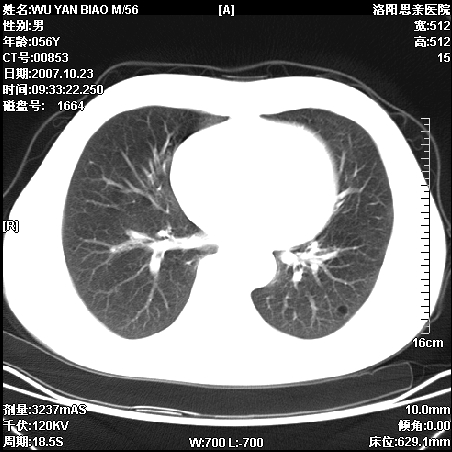

标题: CT10160:M56Y,体检发现,病人无不适,病人随访中 [打印本页]

标题: CT10160:M56Y,体检发现,病人无不适,病人随访中

后上纵隔占位,与肺交界清,宽基底附着脊柱,密度均匀,局部骨质无明确改变.

考虑;神经源性肿瘤,---起源交感n链?,不除外肠源性囊肿.

后纵隔神经原性肿瘤可能性大,孤立性胸膜间皮瘤待排.

1、病灶在后纵隔脊柱旁沟内,此处是神经原性肿瘤的好发部位

2、病灶边缘光滑整齐,更说明病灶来于纵隔,由于有胸膜的包裹所以才导致这么光滑的边缘

3、病灶内的密度均匀